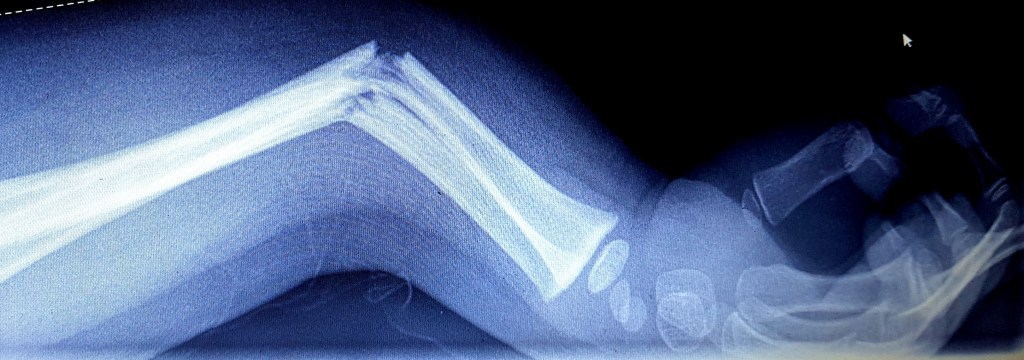

Op de foto’s is het overduidelijk: een twijgbreuk van de spaakbeen en ellepijp. Omdat Noëlle een uurtje geleden geluncht heeft, zijn er nu twee vervolgopties: Één: de arm wordt gezet zonder ‘roesje’. Twee: de arm wordt over vier uren pas gezet, maar dan mét ‘roesje’. Met een ‘roesje’ bedoelen ze een hele lichte narcose. Omdat Noëlle niet zo lang geleden gegeten heeft, willen ze die nu dus niet geven. (Standaard procedure.) Maar jemig, wat een beslissing! De arm zonder verdoving zetten lijkt me niet menselijk, maar vier uren wachten ook niet! Kiezen uit twee kwaden… We kiezen de eerste.

De arm wordt gezet en ingegipst door een iets te vrolijke arts die – zo vermoed ik – Noëlle op die manier probeert op te beuren. Maar ik vind hem helemaal niet leuk. Ik vind hem een verwaande eikel, maar ja… Hij is wel arts. Hij wikkelt de rol gips (net als een rol verband) van boven naar beneden om Noëlles arm en eindigd bij haar hand. Iedere keer als hij de rol tussen haar duim en wijsvinger doordrukt, gilt ze het uit van de pijn. “Nou, niet zo aanstellen hoor!” Roept hij jolig. Niet zo aanstellen? Zei hij dat nou écht? Ik werp hem een vernietigende blik toe. “Tsja,” zegt hij een tikkeltje verongelijkt na het zien van mijn dodelijke uitdrukking. “Na het zetten mag het niet zoveel pijn meer doen hoor.” Ik schud mijn hoofd. Ik vind hem écht een eikel, maar ik laat de stituatie – en de arts – voor wat het is en focus me op het troosten van mijn meisje. Wat een dag…

Na twee weken komen we terug voor controle. Niet op de eerste hulp natuulijk, maar op de polikliniek orthopedie. Wanneer ik de arts daar vertel dat Noëlle nog steeds veel pijn heeft, vertrouwt ze het niet en laat een extra foto maken. Wat blijkt? Haar duim is ook gebroken! Ik ben ik shock! Het arme kind! En dan herinner ik me die arrogante arts weer van de Eerste Hulp. “Niet zo aanstellen!” Riep die en onderwijl dat kleine duimpje, nee, gebróken duimpje steeds maar aan de kant drukkend met die grote rol gips! Dáárom gilde ze zo hard! Hij heeft gewoon niet goed op de foto’s gekeken. De lul! Ik kan hem wel vermóórden! Wandelend door de vele gangen op de terugweg van de poli, kijk ik extra goed om me heen. Vurig hoop ik dat hem tegenkom, zodat ik die zelfingenomen grijns van z’n smoel kan slaan!